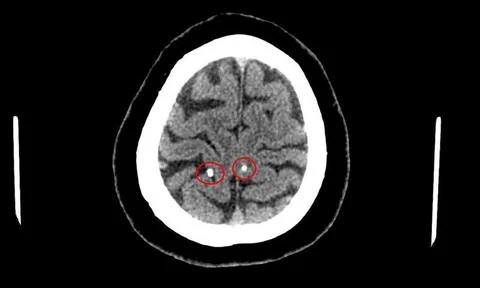

Sán làm tổ trong não vì thói quen ăn đồ sống

Đi khám vì thấy nhức đầu nhiều, người bệnh được chụp cắt lớp vi tính sọ não, kết quả cho thấy hình ảnh nang ký sinh trùng trong não.

Triệu chứng tương đồng giữa u não và nhiễm sán lợn trên não

Nhiều trường hợp bệnh nhân nhiễm sán lợn trên não đã bị nhầm lẫn với các bệnh khác dẫn đến điều trị muộn, thậm chí hoang mang vì tưởng mắc u não.